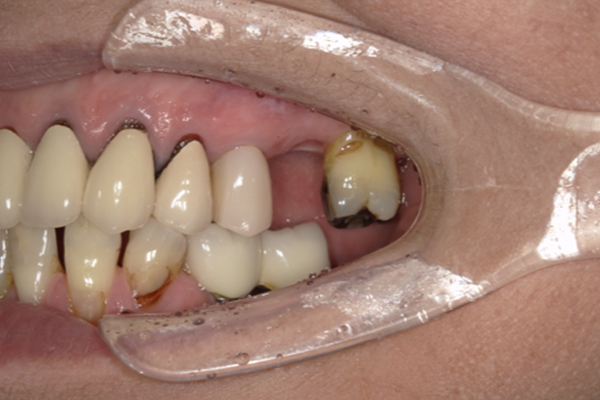

| 主訴 | 奥歯で噛めない、顎が痛い |

|---|---|

| 治療内容 | 奥歯のインプラント治療、前歯・奥歯の被せ物治療 |

| 治療期間 | 6ヶ月 |

| 治療費 | 350万円 |

| 治療リスク | 被せ物をつけた初期の段階で歯がしみることがある(時間とともに改善する) インプラント治療後に3日程度痛みと腫れを伴うことがある |